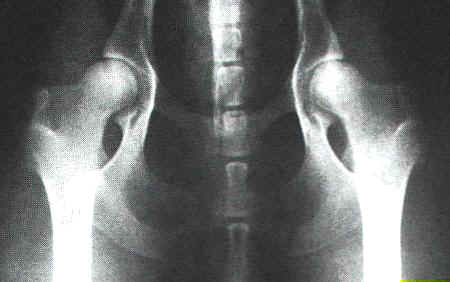

normale HD - Aufnahme bei einem Schäferhund |